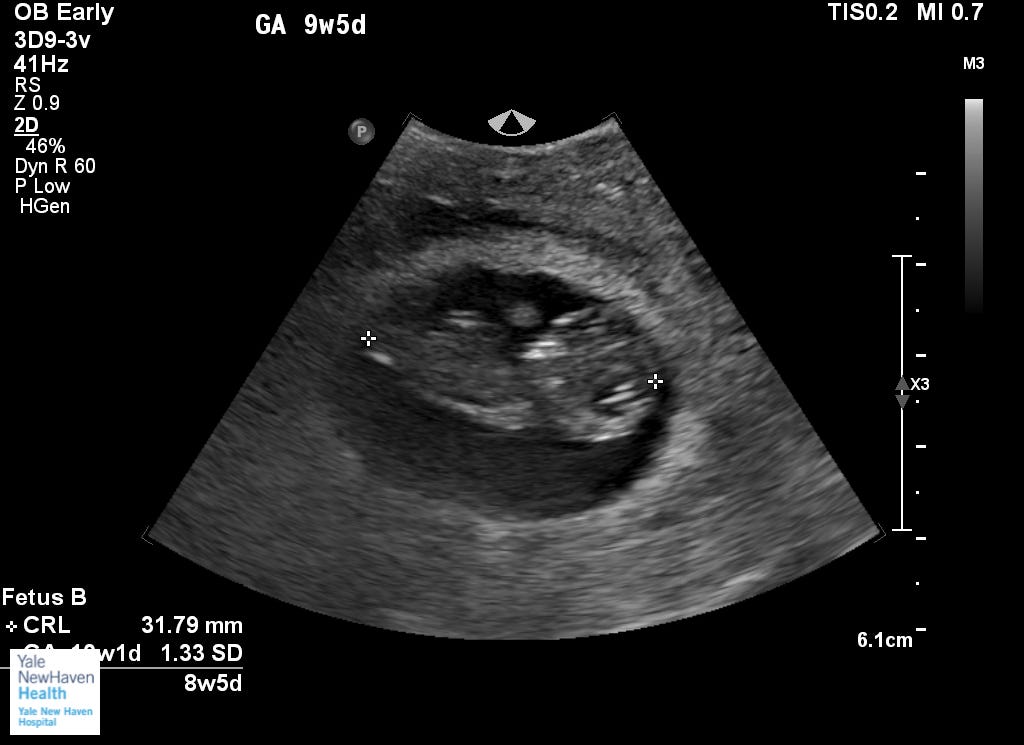

We were doing an early ultrasound and the tech at the fertility clinic went “Oh!” And there was a second gestational sac, in which a second baby might go. That there was a second sac was actually better than the alternative - “multiples” increase miscarriage risk and complications in general, and those risks are particularly high when twins share the same gestational sac. (A loss of one of the embryos can trigger a response that disposes of the other one too, which feels like another level of biological cruelty to me.) But it looked like there was nothing in that gestational sac, making it an “anembryonic” second pregnancy. We were told it would break apart and be reabsorbed in time, nothing to get attached to, nothing to be worried about. But then, another ultrasound, and there was definitely a little embryo inside, looking quite like its sibling, just small. Unlike with its twin, though, there was no detectable heartbeat. Probably not viable, probably not, probably not. Probably no second baby, probably not, probably not. We were told it would break apart and be reabsorbed in time, nothing to get attached to, nothing to be worried about. Like a parent telling their child not to expect snow on Christmas. They got firmer the more time went on in which we shared the Earth with Twin B: don’t get invested. Don’t expect this child to survive. And then there was another ultrasound, and look there, a heartbeat, a little uneven, but strong. The people at Yale were surprised and started hedging their bets, but their company line didn’t change much. It could survive, maybe, impossible to say there was no chance, but still - they stressed that it would very likely break apart and be reabsorbed in time, nothing to get attached to, nothing to be worried about. Don’t get attached. Don’t get attached.